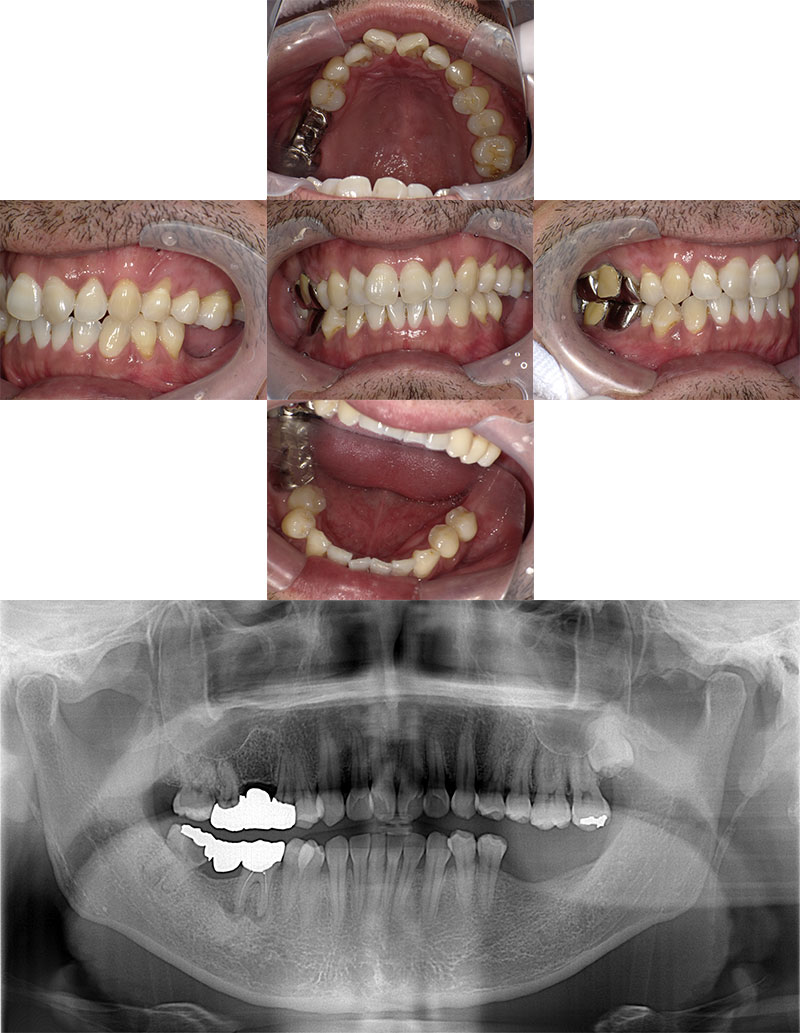

ホワイトニング症例

治療前

Before

治療後

After

年齢 26

性別 女性

主訴 歯を白くしたい